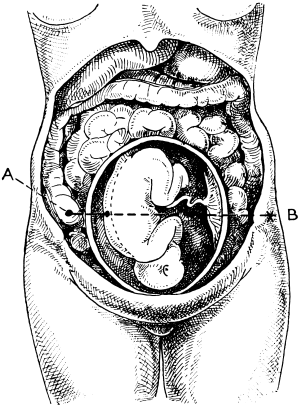

| 23. | A Gravid Uterus in Sagittal Section | 79 |

| 22. | A Uterus distorted by Fibroids | 76 |